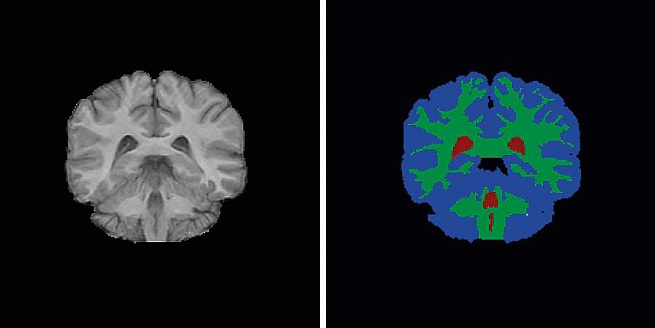

Следующий алгоритм не обладает творческими задатками, зато способен изменить частоту любого видеоряда: из 25 кадров в секунду сделать 270! Компания Nvidia опубликовала в Интернете описание алгоритма в конце 2018 года. Сейчас уже есть его реализация в открытом исходном коде – любой может скачать его и опробовать на домашнем видео с котиками. Работа алгоритма проста: он смотрит на два кадра и пытается составить цепочку снимков, которые подошли бы для промежуточного состояния изображения. Цепочку вычисляет сверточная нейронная сеть U-Net. Изначально она использовалась в медицинских исследованиях для сегментации изображений мозга и печени, чтобы визуально разделить части органов. Когда Nvidia экспериментировала с алгоритмом, первые результаты получились не очень качественными: края движущегося объекта на промежуточных кадрах были размазаны. Но оказалось, что достаточно отдавать каждый новый кадр второму U-Net алгоритму, и эффект размытия пропадает.

Нейронная сеть U-Net обрабатывает изображение, www.medium.com/@keremturgutlu